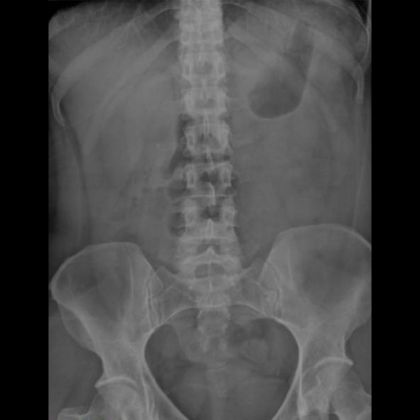

C. Badania diagnostyczne

- Rentgen jamy brzusznej – co można zobaczyć?: Rentgen brzucha może wykazać obecność ewentualnych przeszkód w przewodach żołądkowo-jelitowych, zawałów, czy perforacji.

- Tomografia komputerowa w diagnozowaniu niedrożności: Tomografia komputerowa może dostarczyć bardziej szczegółowych obrazów od rentgenu i pomóc w dokładniejszym określeniu przyczyny niedrożności.

- Ultrasonografia i jej rola w szybkim rozpoznaniu: Ultrasonografia może być użyteczna w szybkim rozpoznaniu niedrożności jelit poprzez wizualizację struktur wewnętrznych brzucha i ocenę przepływu krwi do jelit.